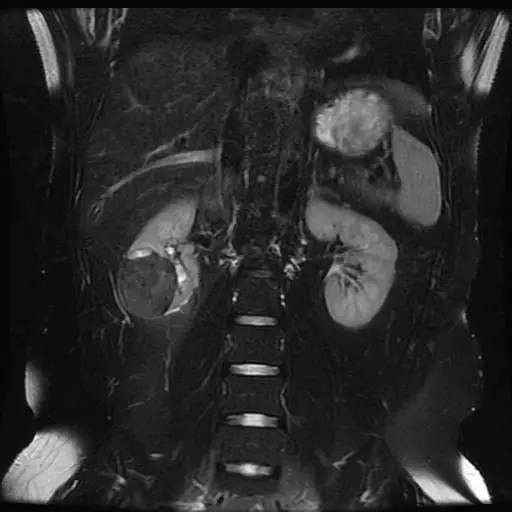

右肾中下部见类圆形约52*49*59毫米类圆形短和稍长T1、短和长T2异常信号肿块,可见假包膜,DWI呈晕环结节状稍高和稍低信号,反相位图像病变信号未见异常减低;皮质期病变未见异常强化,髓质期及延迟期持续轻度强化;病变内小部分区域未见强化。所见肝胆、胰腺、脾脏及双侧肾上腺未见异常,肝门、肾门及所见腹膜后未见异常肿大淋巴结影。

影像诊断:右肾中下部少血供肿块伴出血、坏死和囊变,考虑:恶性肿瘤,以肾癌(非透明细胞癌)可能性最大,不能完全除外表现不典型的血管平滑肌脂肪瘤。